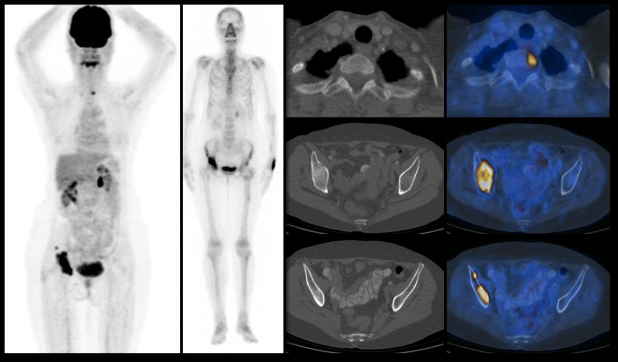

Figura 4.

Figura 4. Paciente de 62 años cáncer de mama de 18 años de evolución, que presenta lesiones blásticas hipermetabólicas en articulación coxofemoral derecha, las que además expresan incremento intenso en la actividad osteoneogénica (imágenes de la izquierda, PET y gammagrama óseo respectivamente). Sin embargo, el estudio PET-CT con FDG también evidencia zonas focales de incremento metabólico en cuerpo vertebral de T2 e ilíaco derecho, (columna de la derecha) que no muestran cambios morfológicos y no son identificadas en el rastreo óseo con MDP.